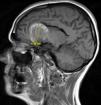

Más datosMujer de 49 años que sufrió una primoconvulsión. Se realizó una TC de cráneo (fig. 1) que objetivó un aneurisma gigante en la arteria carótida interna (ACI) izquierda, trombosado de forma subtotal (no captaba contraste en el angio-TC). Se decidió realizar una arteriografía (fig. 2) que describía un gran aneurisma carótido-oftálmico izquierdo, con una mínima porción permeable (8×5mm), el resto lo describen trombosado. Durante la arteriografía hizo focalidad con hemiparesia y desviación de comisura vocal, con vasoespasmo arteriográfico, que cedió tras administrar verapamilo. Se realizó una RM (fig. 3) que describía el aneurisma con localización paraselar frontal izquierda de 4,2×3,9×3,6cm con origen en el top de la ACI izquierda, presentando efecto masa sobre ambas arterias cerebrales anteriores, arteria cerebral media izquierda, así como compresión y desplazamiento derecho de ambas astas frontales. En el estudio de angio-RM se delimitó una dilatación sacular de 9mm en la porción supraclinoidea de la ACI izquierda, localizada en el tercio inferior del seno de la lesión descrita. Sugieren diagnóstico diferencial con rotura contenida del aneurisma. Se decidió intervención quirúrgica de clipado del aneurisma, que confirmó trombosis parcial del mismo con cápsula íntegra. Tras esto, la paciente se encuentra sin focalidad y como única complicación posterior ha desarrollado un síndrome pierde-sal.